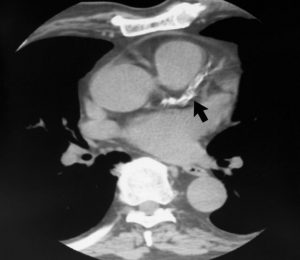

Severe Calcification